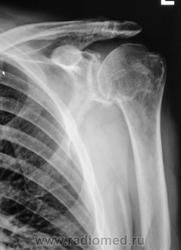

Пациент направлен на рентгенографию плечевого сустава хирургом.

При обращении пациент предъявляет жалобы на боли в плечевом суставе. Хирург поликлиники пациента не осматривал, а сразу соорудил направление на рентгенологическое исследование.

На следующий день пациент был осмотрен хирургом, и был направлен на рентгенографию другого плечевого сустава.

В левом суставе - вероятно изменения за счёт артроза, обызвествления связок

В правом - последствия травмы (подвывих, перелом головки?)

Травму пациент не помнит...

Двусторонний деформирующий остеоартроз: справа усилен верхним подвывихом с образованием неартроза с акромиальным отростком.

2-сторонний ДОА, справа подвывих, неоартроз + калькулезный (известковый) бурсит(возможно тоже 2-сторонний)